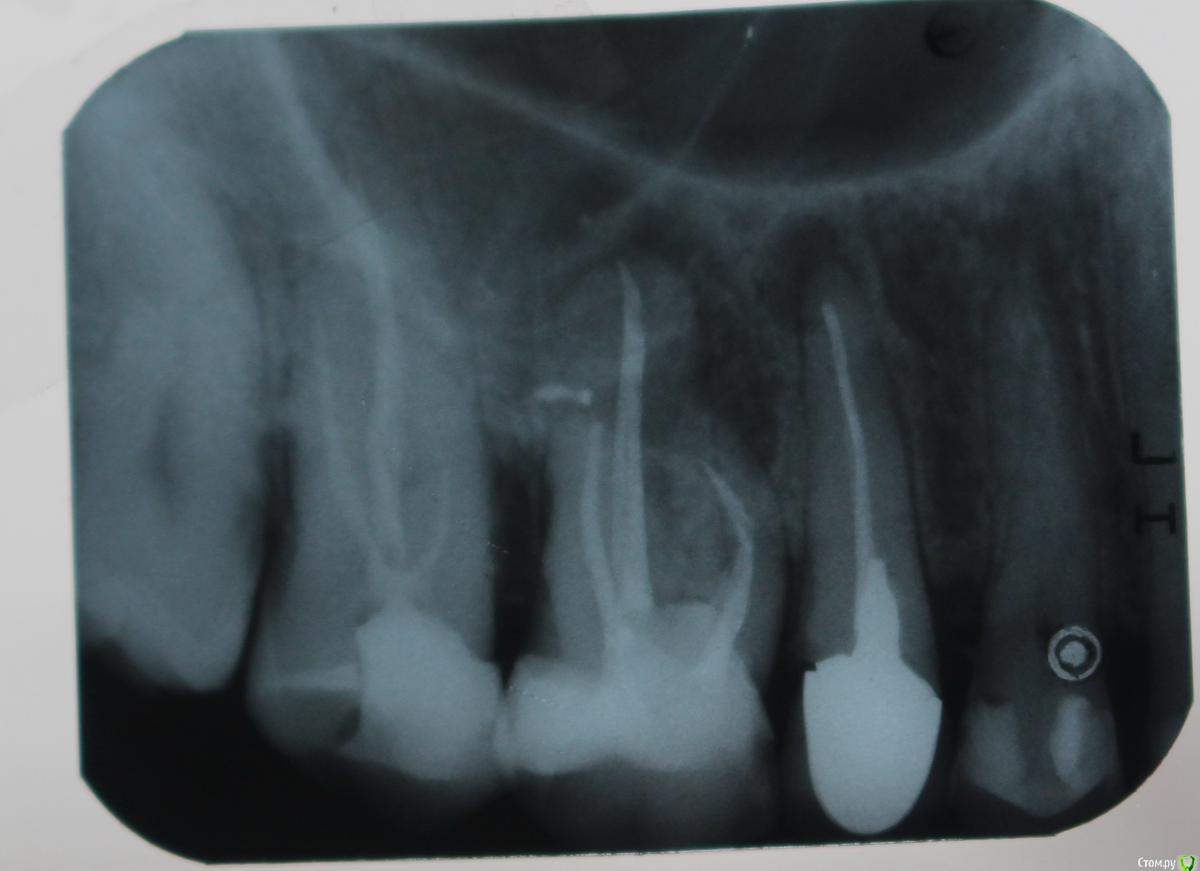

стихия Опубликовано 3 июля, 2017 Поделиться Опубликовано 3 июля, 2017 Здравствуйте, уважаемые стоматологи! Очень прошу вашей помощи. Ситуация такая: год назад пломбировали мне каналы в 26-м зубе. Через пол-года начала чувствовать десну и щеку, сам зуб не болел. Пошла к врачу, сделали снимки, сказал гранулема на 25(про 26-й ничего не сказал), можно наблюдать, если воспалится - сделать резекцию верхушки корня. На прошлой неделе вспухла немного щека и заложило гайморовую пазуху. Опять сделали снимок и сказали удалять 26, спасти зуб нельзя, а в 25 лечить кисту. Я в шоке. Удалять не хотелось бы. Очень прошу посмотреть мои снимки и дать совет: можно ли вылечить кисту 26-го без удаления? Сейчас опухоль спала и зуб практически не беспокоит. Что будет, если вообще его пока не трогать? Выкладываю снимки, сделанные: 1. год назад 2. пол-года назад 3. на прошлой неделе.1. http://s015.radikal.ru/i330/1707/e8/be0d848983dd.jpg2. http://s018.radikal.ru/i508/1707/f4/68ec5e31521b.jpg3. http://s019.radikal.ru/i608/1707/17/603d3bfcc4b7.jpg Ссылка на комментарий

DmitrySH Опубликовано 4 июля, 2017 Поделиться Опубликовано 4 июля, 2017 Делать надрез в десне или все-таки через каналы? И еще: были ли уже видны гранулемы год назад, когда пломбировали каналы (снимок 1) или они появились позже? Или через каналы или удалять. Год назад была уже была гранулема. Ссылка на комментарий